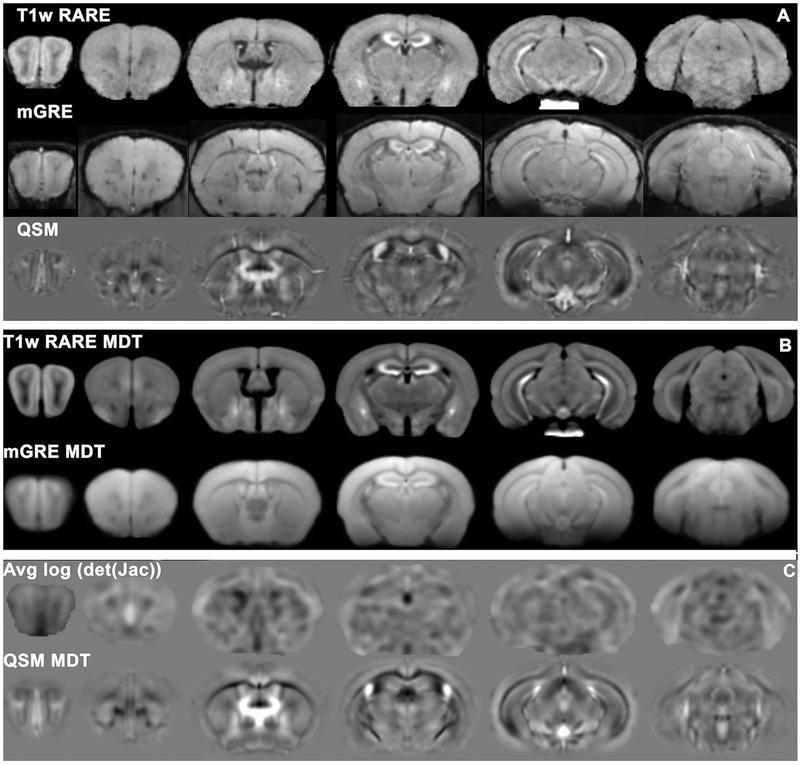

Magnetic resonance imaging of mouse brain networks plasticity following motor learning

Manuscript titled "Magnetic resonance imaging of mouse brain networks plasticity following motor learning" by Alexandra Badea et al. has been published in PLOS ONE.